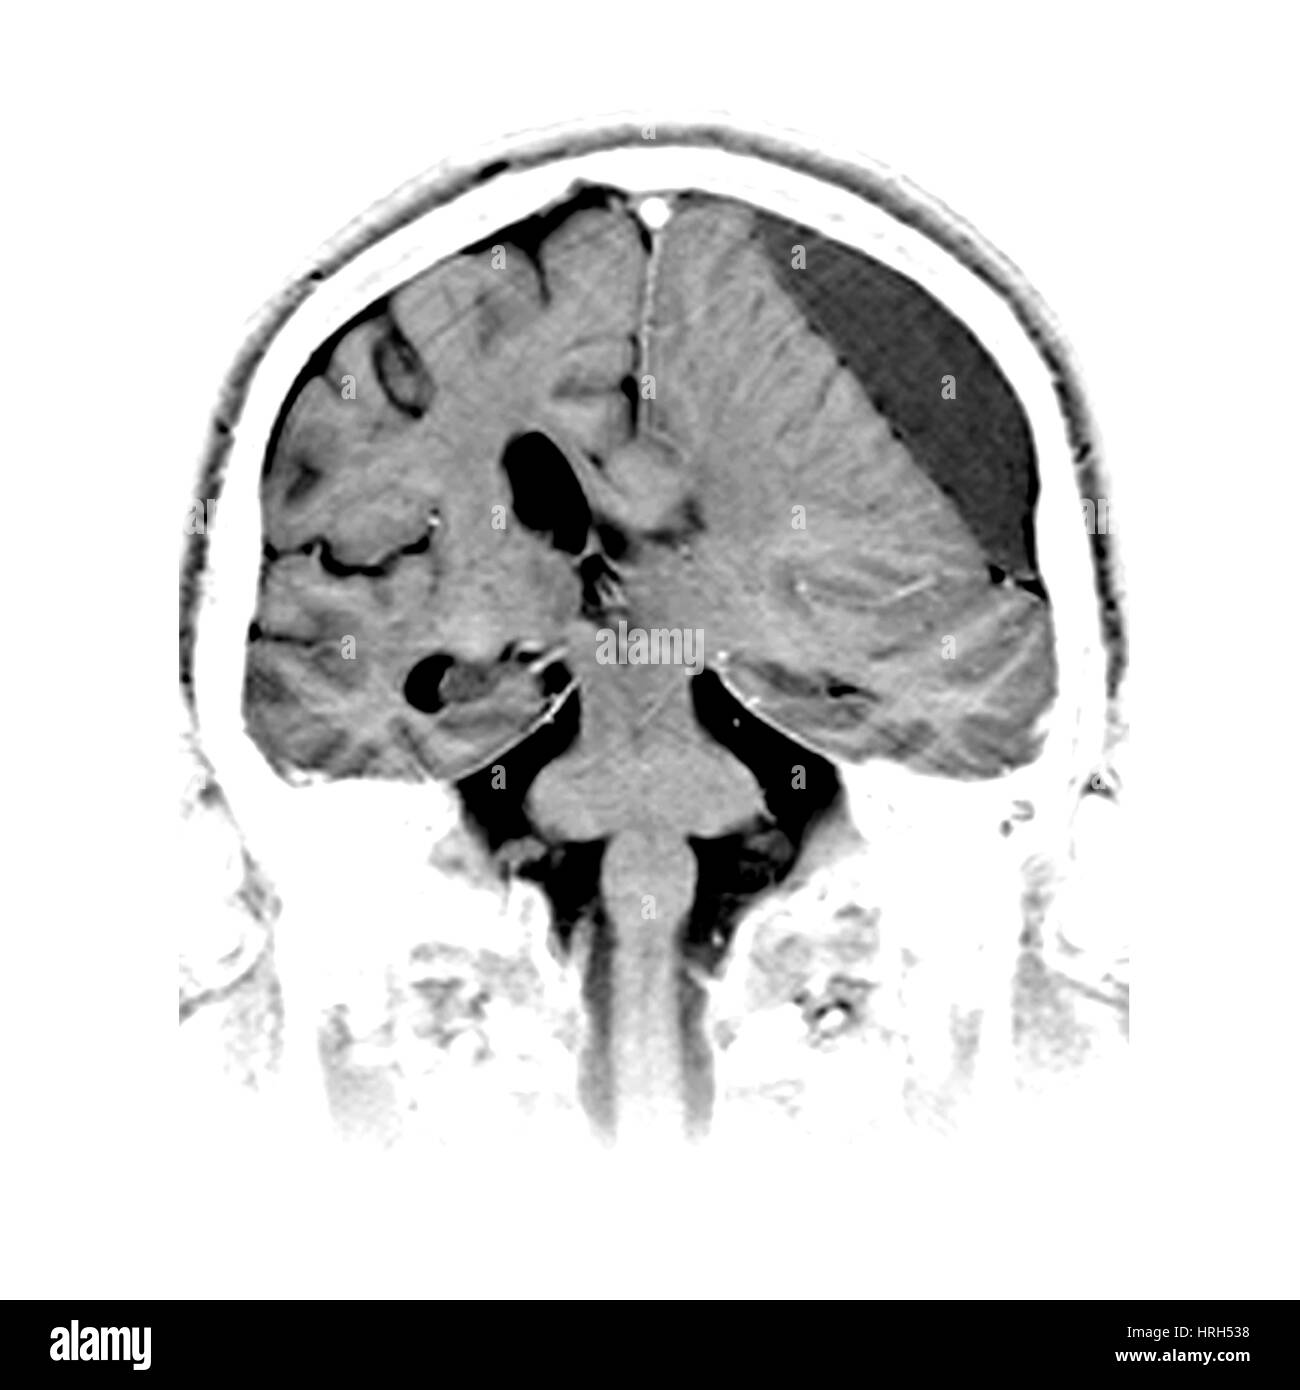

A hematoma occurs when blood leaks from a large blood vessel In this article, learn about the causes and symptoms of hematomas as well as the different types and when to see a doctor. Sintomatologia dell'ematoma traumatico epidurale La diagnosi di ematoma epidurale non presenta di solito particolari difficoltà nelle forme tipiche, in cui è sempre presente un intervallo libero tra la risoluzione del quadro commotivo posttraumatico e l'instaurarsi dei segni di ipertensione endocranica ingravescente. Ematoma subdurale acuto, che causa compressione e dislocazione del cervello L'operazione deve essere eseguita il prima possibile dopo la lesione Prima veniva rimosso l'ematoma subdurale, migliore era l'esito Ematoma subdurale subacuta con aumento della sintomatologia focale e / o segni di ipertensione endocranica.

In medicina, l'ematoma subdurale è anche noto come emorragia subdurale Cause Un ematoma subdurale si forma quando uno o più vasi sanguigni, presenti nello spazio subdurale, si rompono, provocando la fuoriuscita di sangue ( ictus emorragico ). L’ematoma subdurale cronico rappresenta una delle patologie più comuni che si riscontrano in un reparto di neurochirurgia Il suo trattamento chirurgico, di solito semplice, è d’altra parte affidato ai più giovani, nella misura in cui tale intervento è uno dei pochi di cui l’interno ha una buona esperienza. Per ematoma subdurale si intende un accumulo di sangue nella regione situata tra le due meningi cerebrali, il quale può essere di natura acuta o cronica Da che cosa è causato?.

L’ematoma subdurale cronico rappresenta una delle patologie più comuni che si riscontrano in un reparto di neurochirurgia. What is an Acute Subdural Hematoma?. It Secono le ricerche degli AA, è da ritenere accertato che l'inizio delle emorragie nell'ematoma subdurale cronico avvenga poco tempo dopo il trauma springer en According to the AA's observations, it is taken for granted that the hemorrhage in chronic subdural hematomatas begins shortly after the trauma.